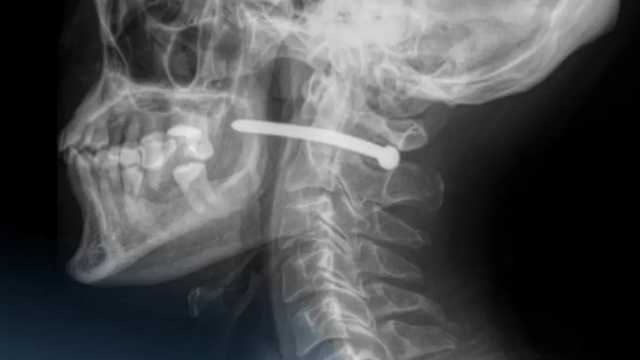

В Петропавловске хирурги многопрофильной городской больницы скорой медицинской помощи удалили гвоздь из шеи 51-летнего мужчины, пишет Qostanay.TV со ссылкой на Информбюро.

Гвоздь из пневматического пистолета попал в организм мужчины во время ремонта, по неосторожности.

Врачи провели удаление инородного тела, ревизию и обработку раны и назвали «чудом» и «везением», что жизненно важные структуры не были задеты.